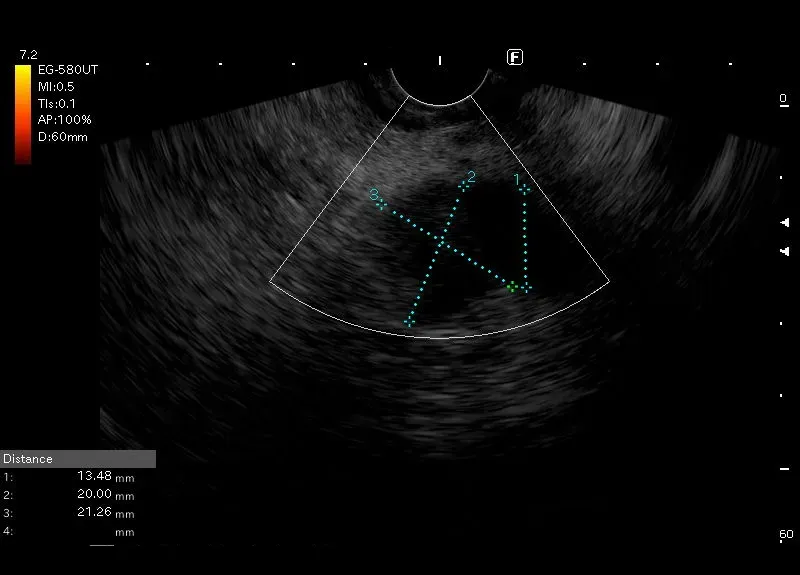

Poszerzenie przewodu Wirsunga do 14 mm, tuż za zmianą położoną w głowie trzustki.

Zmian powodująca ”ucisk ”na przewód  Wirsunga ma niejednorodnie obniżoną echogeniczności, nierówne zarysy  i wielkości około 23/30mm. Obraz zmiany a także dyskretny przepływ obwodowy w opcji power doppler i kodowanie się na niebisko „ twarda” w elastografii przemawiać mogą za jej nowotworowym charakterem.